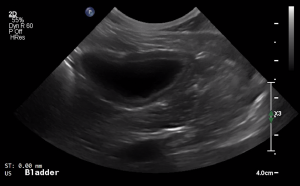

SIMON Ultrasound Database

This ultrasound database is a free resource for students and doctors!

Our collection includes videos of dogs, cats, horses, cows, humans, and many other species!